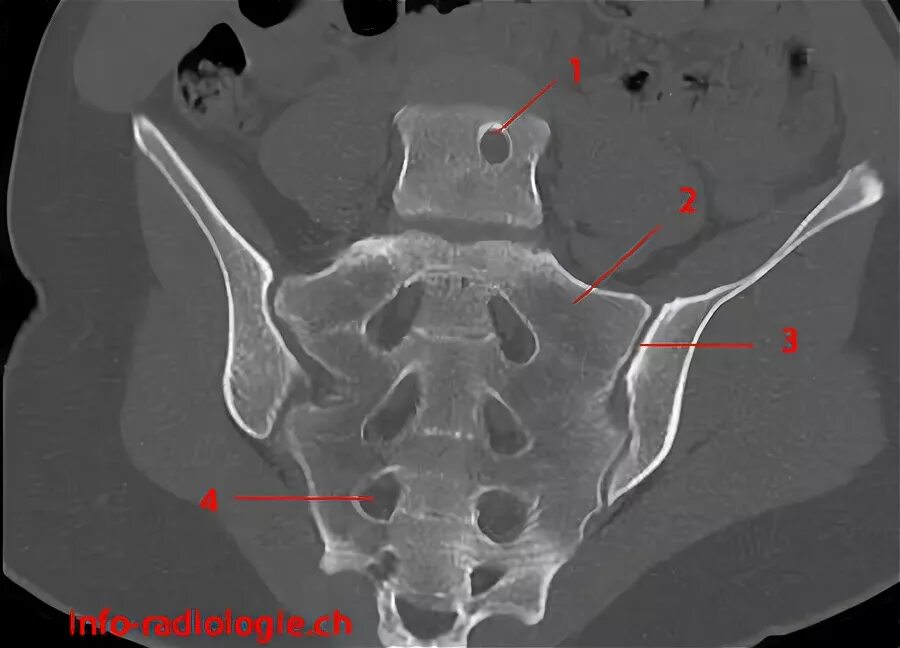

Сакроилеит на кт